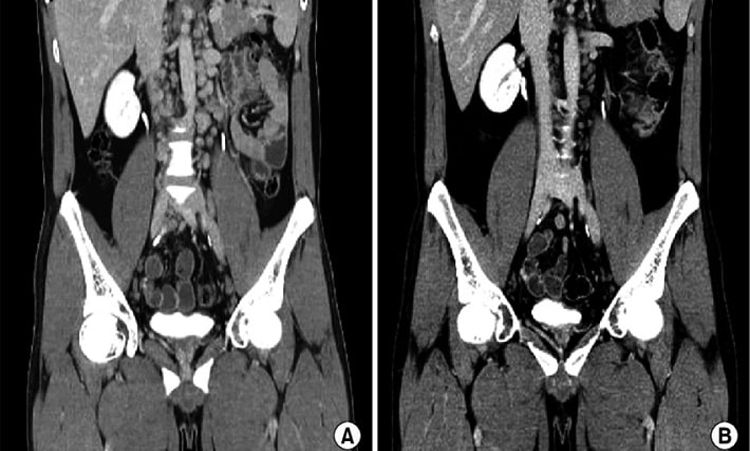

سی تی اسکن اسپیرال در بسیاری از زمینههای پزشکی کاربرد دارد. یکی از مهمترین کاربردها، تشخیص بیماریهای گوارشی است. این روش میتواند به شناسایی مشکلاتی مانند آپاندیسیت، تومورهای روده و بیماریهای التهابی روده کمک کند. همچنین، سی تی اسکن اسپیرال میتواند در ارزیابی عوارض پس از جراحیهای شکمی و لگنی نیز مؤثر باشد و به پزشکان در برنامهریزی برای درمانهای بعدی یاری رساند.

همچنین، این روش در تشخیص بیماریهای کبد و کیسه صفرا نیز کاربرد دارد. با استفاده از سی تی اسکن اسپیرال، پزشکان میتوانند تومورهای کبدی، سنگهای صفراوی و سایر اختلالات کبدی را شناسایی کنند. این اطلاعات به پزشکان کمک میکند تا تصمیمات بهتری در مورد درمان و مدیریت بیماریهای کبدی اتخاذ کنند و در نتیجه به بهبود نتایج درمانی بیماران کمک کنند.

در مقایسه با روشهای سنتی که تنها تصاویری دو بعدی تولید میکنند، سی تی اسکن اسپیرال با چرخش تیوب اشعه ایکس به دور بیمار، امکان تولید تصاویری سهبعدی را فراهم میکند. این ویژگی به پزشکان این امکان را میدهد که ساختارهای داخلی بدن را به دقت بررسی کنند و در نتیجه تشخیصهای دقیقتری انجام دهند. این روش به ویژه در بررسی نواحی شکم و لگن که شامل اندامهای حساسی مانند روده، کبد و مثانه است، بسیار مؤثر است.